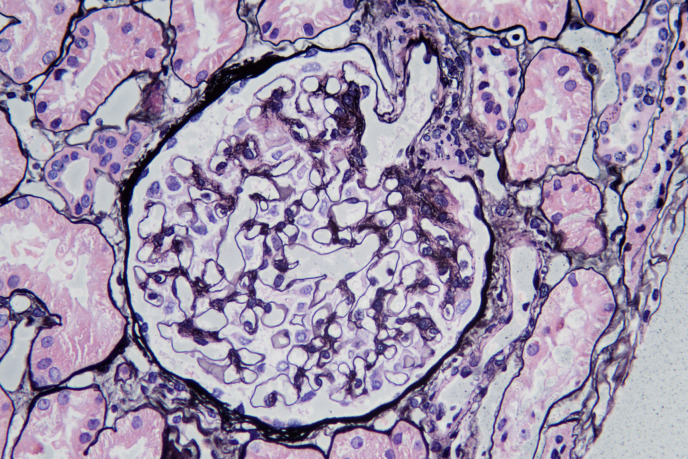

成人节段性膜性肾小球病变。

Introduction: The clinicopathological features of segmental membranous glomerulopathy (SMGN) have not been well characterized. The aim of this study was to investigate the prevalence and clinicopathological features of SMGN in adults.

Methods: Adult patients with biopsy-confirmed SMGN in the native kidney at our center between January 2017 to September 2020 were identified. The clinicopathological features of SMGN were collected. The glomerular deposition of IgG subclasses, M-type phospholipase A2 receptor 1 (PLA2R), thrombospondin type 1 domain-containing 7A (THSD7A), and neural epidermal growth factor-like 1 protein (NELL1) were tested. Clinical and pathologic features were comparable between NELL1-positive and NELL1-negative SMGN.

Results: A total of 167 patients with biopsy-proven SMGN were enrolled. During the same period, 32,640 (33.0%) out of 98,939 renal biopsies were diagnosed with membranous nephropathy (MN) in adults. SMGN accounted for 0.17% of total kidney biopsies and 0.51% of MN in adults. One hundred and fifty (89.8%) cases were isolated SMGN, and 17 (10.2%) cases were complicated with other kidney disease. Clinically, the median age of isolated SMGN patients was 41.5 years, with female (74%) predominance, and 33.1% had full nephrotic syndrome. Pathologically, IgG1 was the dominant subclass (92.5%), followed by IgG4 (45.0%). PLA2R and THSD7A staining were done in 142 and 136 isolated SMGN cases, respectively, in which, all the cases showed negative. NELL1 staining was done in 135 isolated SMGN cases; 58 cases (43.0%) showed positive. Fifty-eight patients (41.1%) had diffuse (≥90%) foot process effacement, and 119 patients (83.8%) had either stage I (38.0%) or stage II (45.8%) membranous alterations in patients with SMGN. Most patients with NELL1-positive SMGN were female. Patients with NELL1-positive SMGN were more likely with lower prevalence of full nephrotic syndrome than NELL1-negative SMGN.

Conclusions: SMGN is a relatively rare pathological type. Majority of patients with isolated SMGN were female, with a median age of 41.5 years, 33.1% had full nephrotic syndrome, absence of PLA2R and THSD7A, 43.0% with NELL1-positive, and mainly stage I or II MN (83.8%). NELL1 is the major target antigen of SMGN in adults.